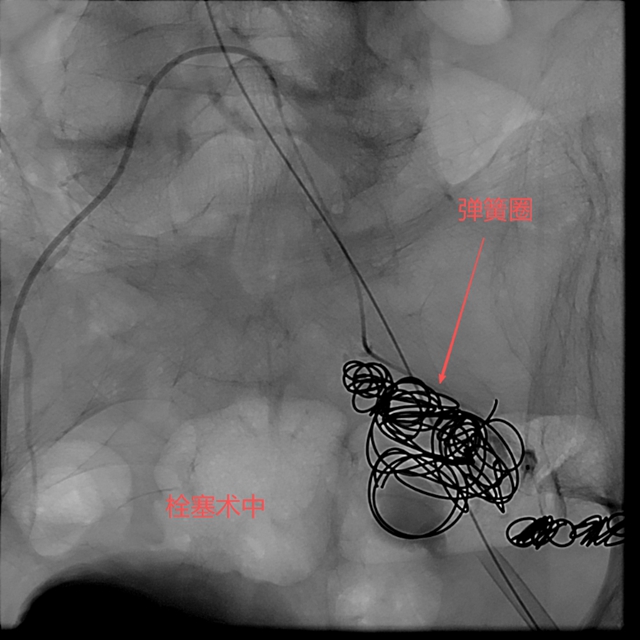

徐燕能博士选择了弹簧圈+医用胶水的复合栓塞技术——这项技术在介入医学界被戏称为“钢筋水泥”结构。“弹簧圈就像钢筋,能够在动脉瘤内形成一个稳定的框架结构;医用胶水则是水泥,填充在弹簧圈形成的框架中,迅速固化形成致密的栓塞体。”

这种组合的优势在于既能快速止血,又能形成长期稳定的栓塞效果,防止动脉瘤再次扩张或破裂。

随着弹簧圈被精准放置到动脉瘤腔内,医用胶水随后注入,两者结合形成了坚固的“钢筋水泥”结构,牢牢封堵了破裂处。